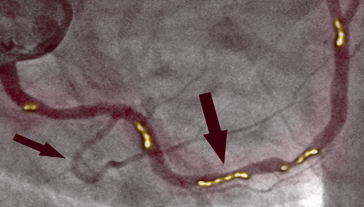

PRIJE TERAPIJE

Na slici lijevo vidimo suženje desne koronarne arterije kod 66-godišnjeg muškarca, dijagnosticirano pomoću invazivne koronarografije. Vidljivo je značajno suženje u proksimalnom segmentu uzrokovano kalcificiranim aterosklerotskim plakom, koji blokira protok krvi.